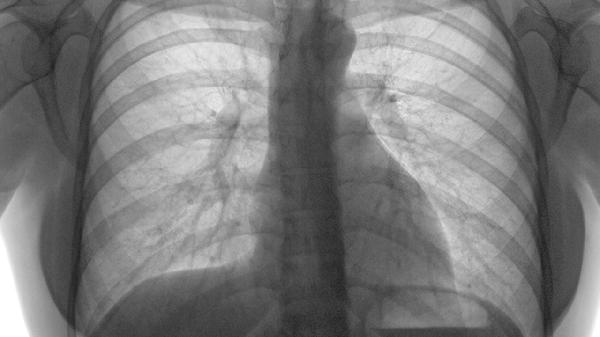

2、症状与诊断方法:肺门癌的症状多与肿瘤对周围组织的压迫有关,常见症状如咳嗽、咳痰、气促和胸痛。为确诊肺门癌,医生通常会建议进行一系列检查,如胸部X线、CT扫描、纤维支气管镜检查和活检等。这些检查可以帮助显示肺部结构的变化,并获取病变组织进行病理分析。